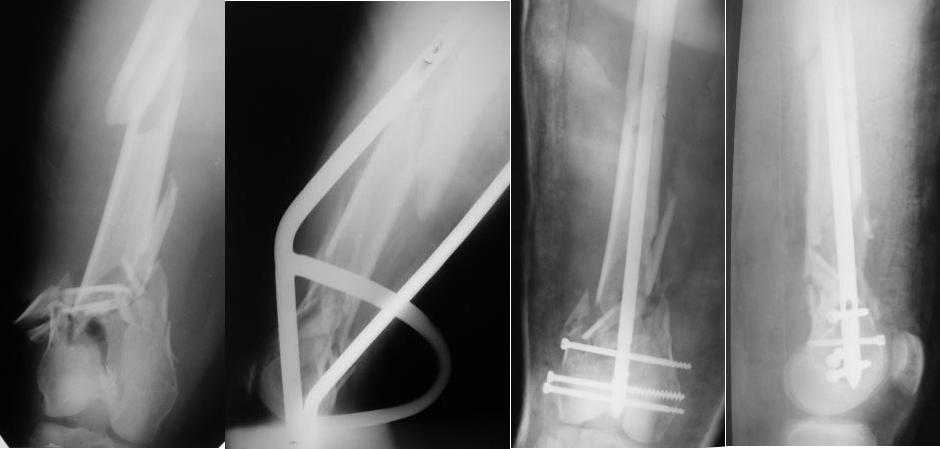

Re: Многооскольчатый перелом бедра

Приносим извенения за недостаток информации. Выкладываю все снимки. Стержень фирмы НПО ДЕОСТ(г.Пущино-на-оке)

-1. стержень в суставе,

Это не критично, в межмышелковой борозде,не на опроной поверхности, выступает из субхондральной кости, не факт что из хряща.Про надколенник Александр Николаевич уже писал.

-2. неправильная длинна винтов,

и толщина тоже. При такой длине хочется помощнее.

-3. ось конечности неправильная,

Вполне прилично. Если в боковой проекции рекувации нет. Где кстати боковая, хочется спросить у постмейкера.

- 4. циркулярная гипсовая повязка после ОС?????

К сожалению, автор умалчивает. Думается, что в данном случае можно и без гипса.

2. Лучше борется с рекурвацией дистального отломка за счет угла Герцога.(В представленном примере "недопобороли")

В данном случае, на мой взгляд, если говорить о гвоздях, предпочтительней антеградное штифтование. Поскольку любая ретроградная конструкция не может иметь столь низкого расположения отверстий для винтов как антеградная из-за резьбового крепления.

Больная госпитализирована с тяжелой сочетанной травмой. Плюсом к перелому бедра имеется разрыв связок коленного сустава.